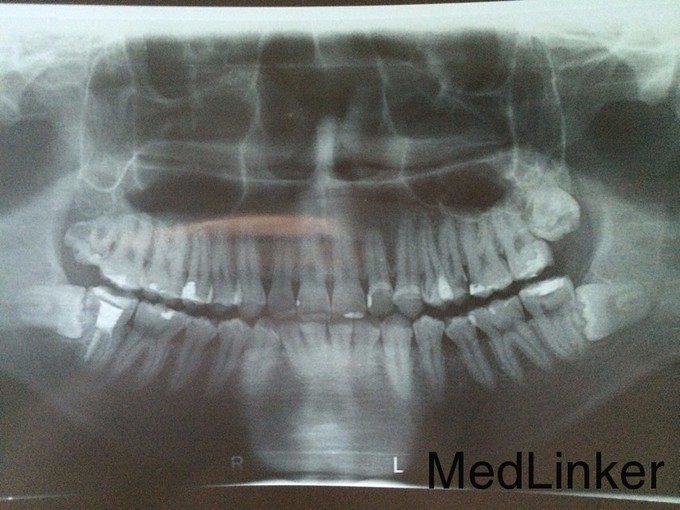

1108下颌阻生齿拔除手术光1

牙齿疼痛要求拔除

下颌阻生齿拔除

1108下颌阻生牙拔除光28

1108下颌水平阻生齿拔除光14